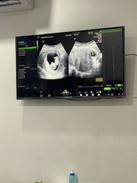

อยากเห็น แผ่นซาว 10+4 w หน่อยจ้าแม่ๆ

ท้องแรกอีแม่ตื่นเต้นไม่ไหว ทีมกันยายน #ทีมกันยายน #ลูกคนคนแรก #ทีมกันยา66 #ท้องแรก

กำหนดคลอด 20 กันยาค่าา🥰 10Wเป๊ะๆ หมอบอกประมาณ 3 ซม. น้องดิ้นตอนซาวด้วยค่ะ 😊

ในภาพตอบ10+5วีค ตอนนี้12+2 แล้วค่ะ กำหนดคลอด2กันยา66

อันนี้ซาวตอน8w ล่าสุด10+1แล้วค่ะ กำหนดคลอด17กันยาจ้า

บ้านนี้ 10 w 6 วันแล้วค้า กำหนดคลอด 12 กันยา

10w6d ค่ะ กำหนดเดือนกันยาเหมือนกัน 💗

ของเราตอน 10w ค่าา